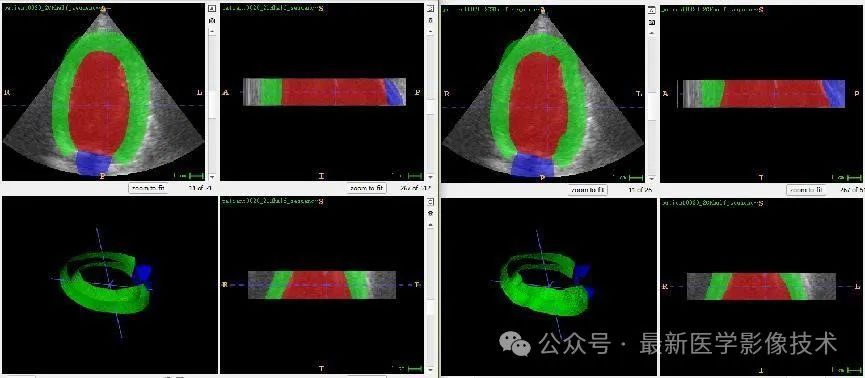

任务二、超声心动图3d结构分割

1、将图像缩放到固定大小512x512x48。图像预处理,再采用均值为0,方差为1的方式进行归一化处理,再将数据分成训练集和验证集,并对训练数据进行数据增强扩增5倍。

2、搭建VNet3d网络,使用AdamW优化器,学习率是0.001,batchsize是1,epoch是300,损失函数采用多类别的dice和交叉熵。

3、训练结果和验证结果

4、验证集部分分割结果

左边是金标准结果,右边是预测结果。